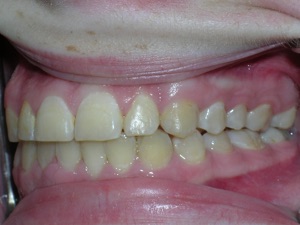

Here’s a fascinating case of a young lady who had a completely blocked out premolar.

With a combination of braces, expansion and trimming we were able to bring it in. Watch!

Here are the results.